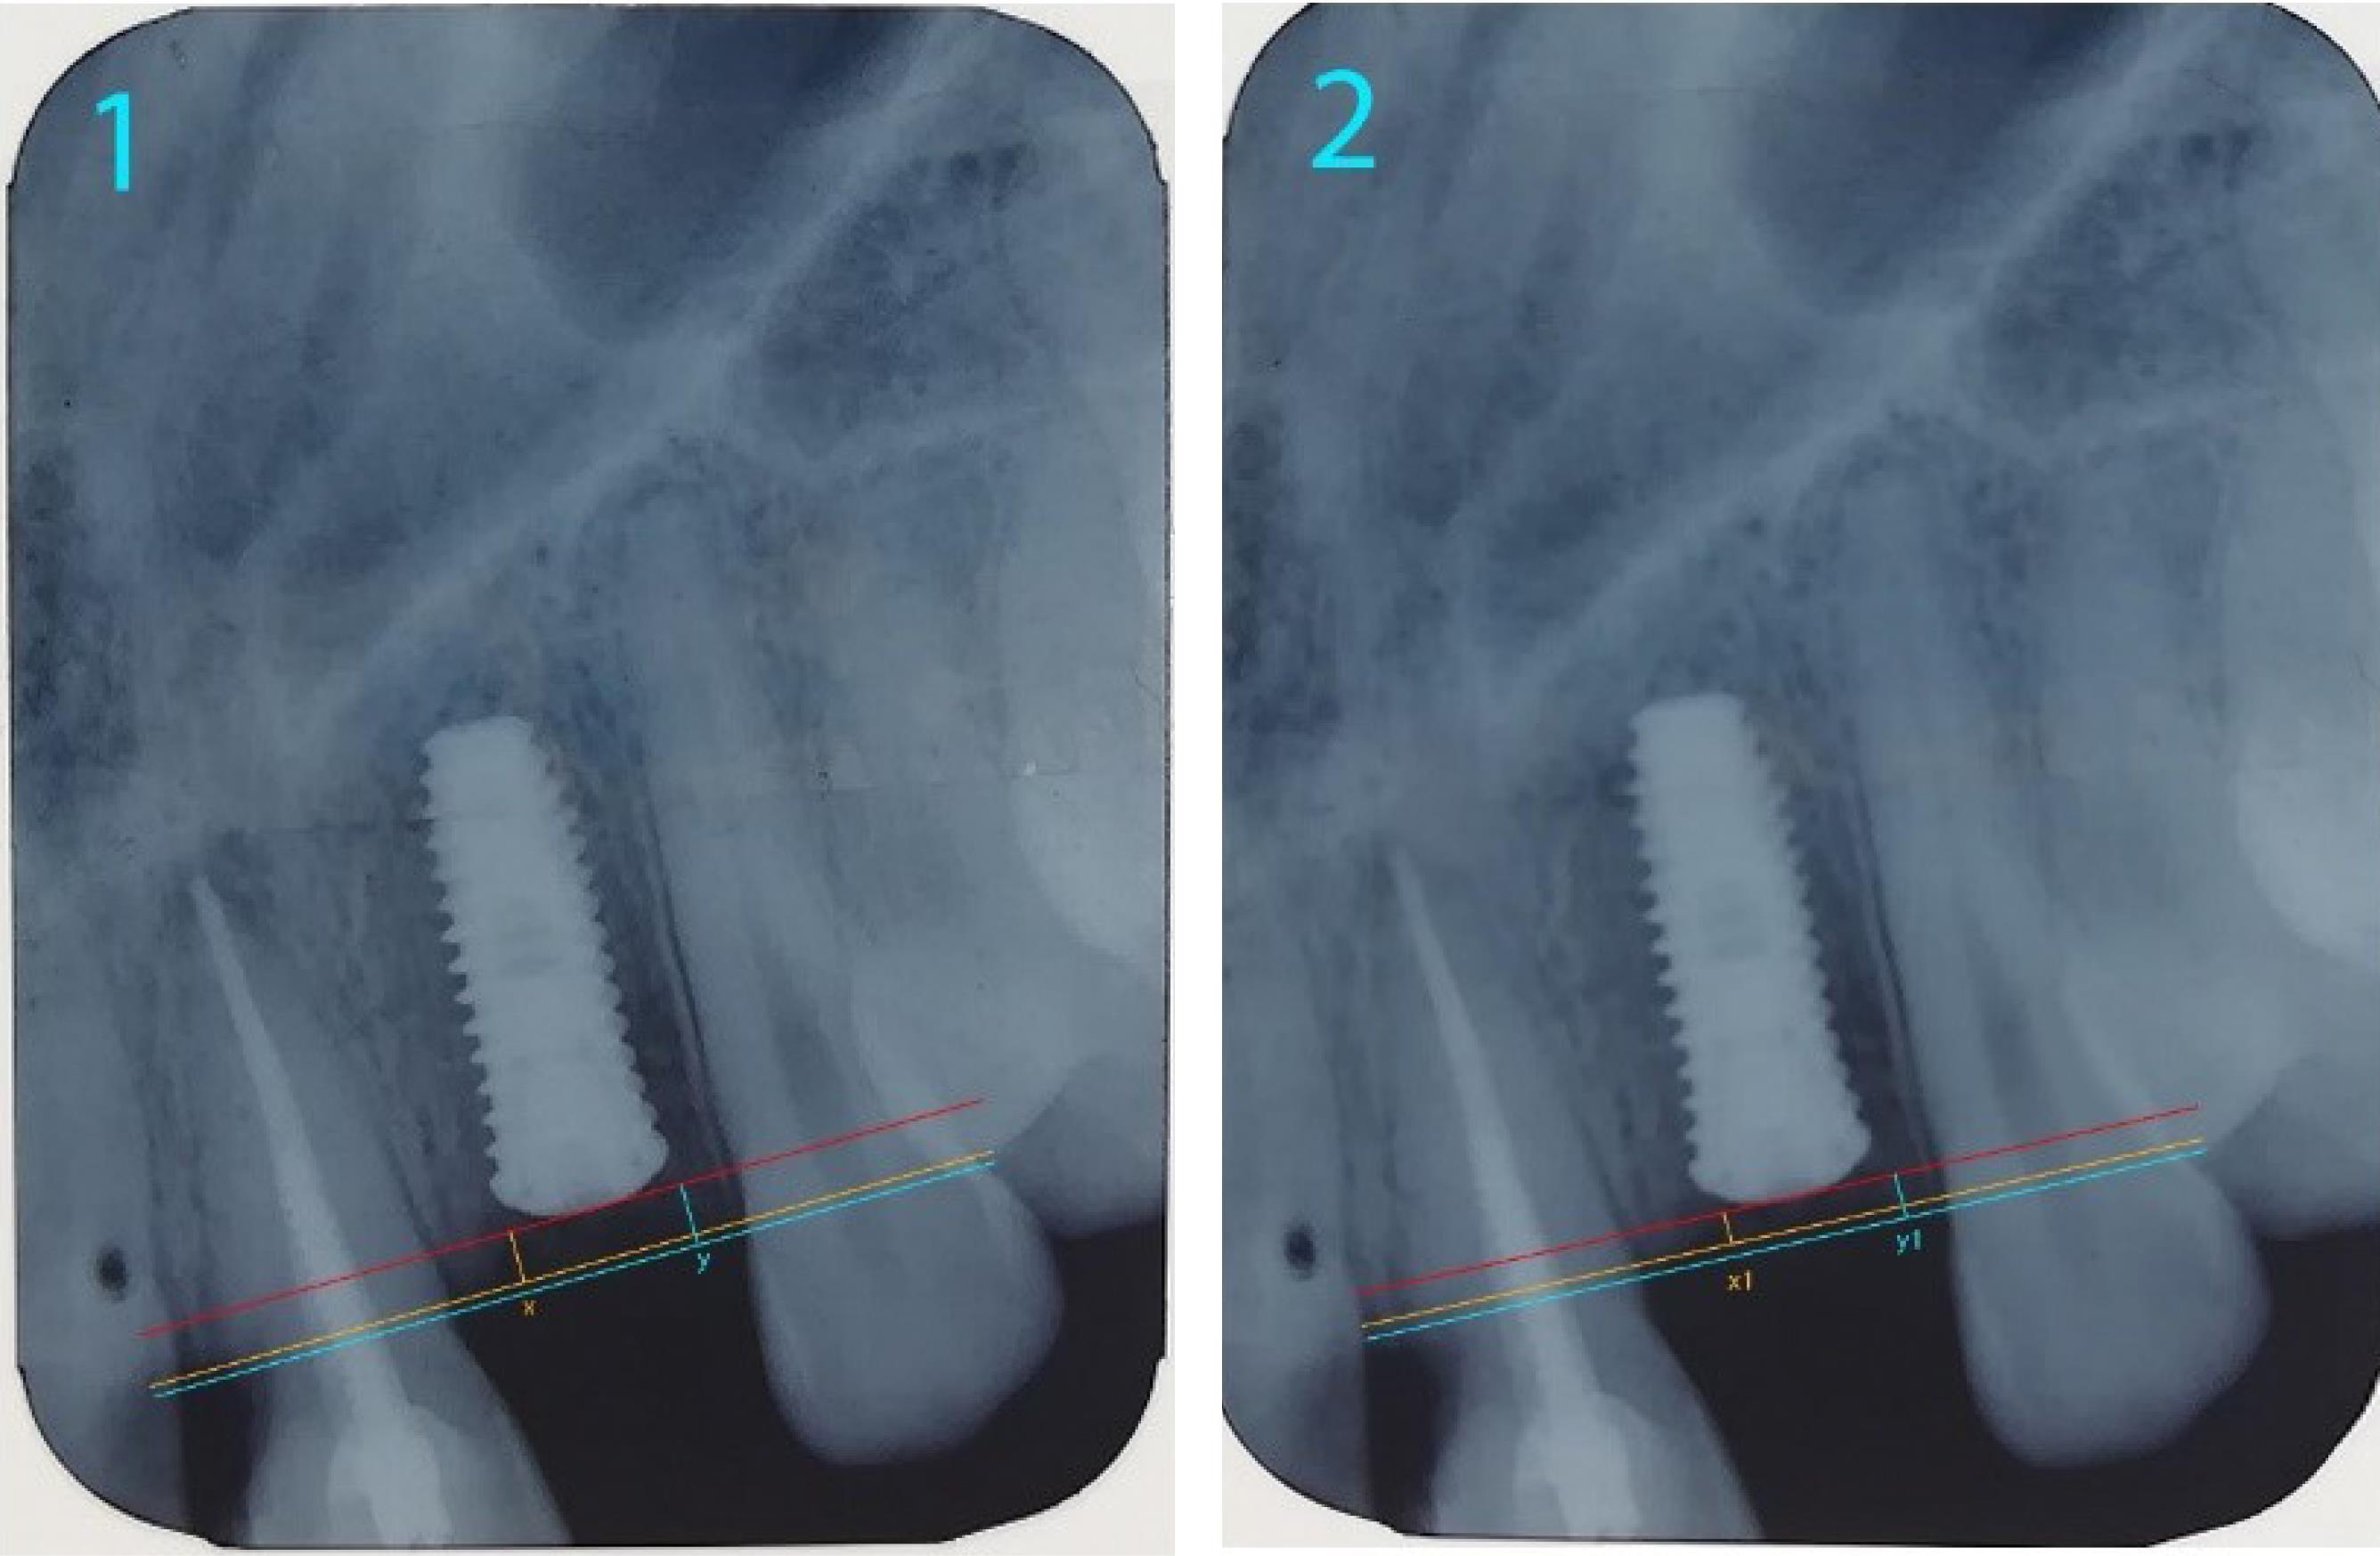

Since the length of the implant used was identified, it was possible to use this length to calibrate the image in computer software. The coronal implant surface was considered the reference line. Two lines were drawn parallel to this line from the crestal bone ridge between the implant and adjacent teeth on both the mesial and distal sides of the implant, and the distance between the two lines and the reference line was measured (Figure 6). By decreasing the bone measurement immediately after implantation and six months later, the amount of bone resorption was achieved on both the mesial and distal sides of the implant (Figure 7).5,13

Figure 6.

Measurement of crestal bone level from the reference line

Figure 7.

Comparison of crestal bone resorption (at 0 month and 6 months)